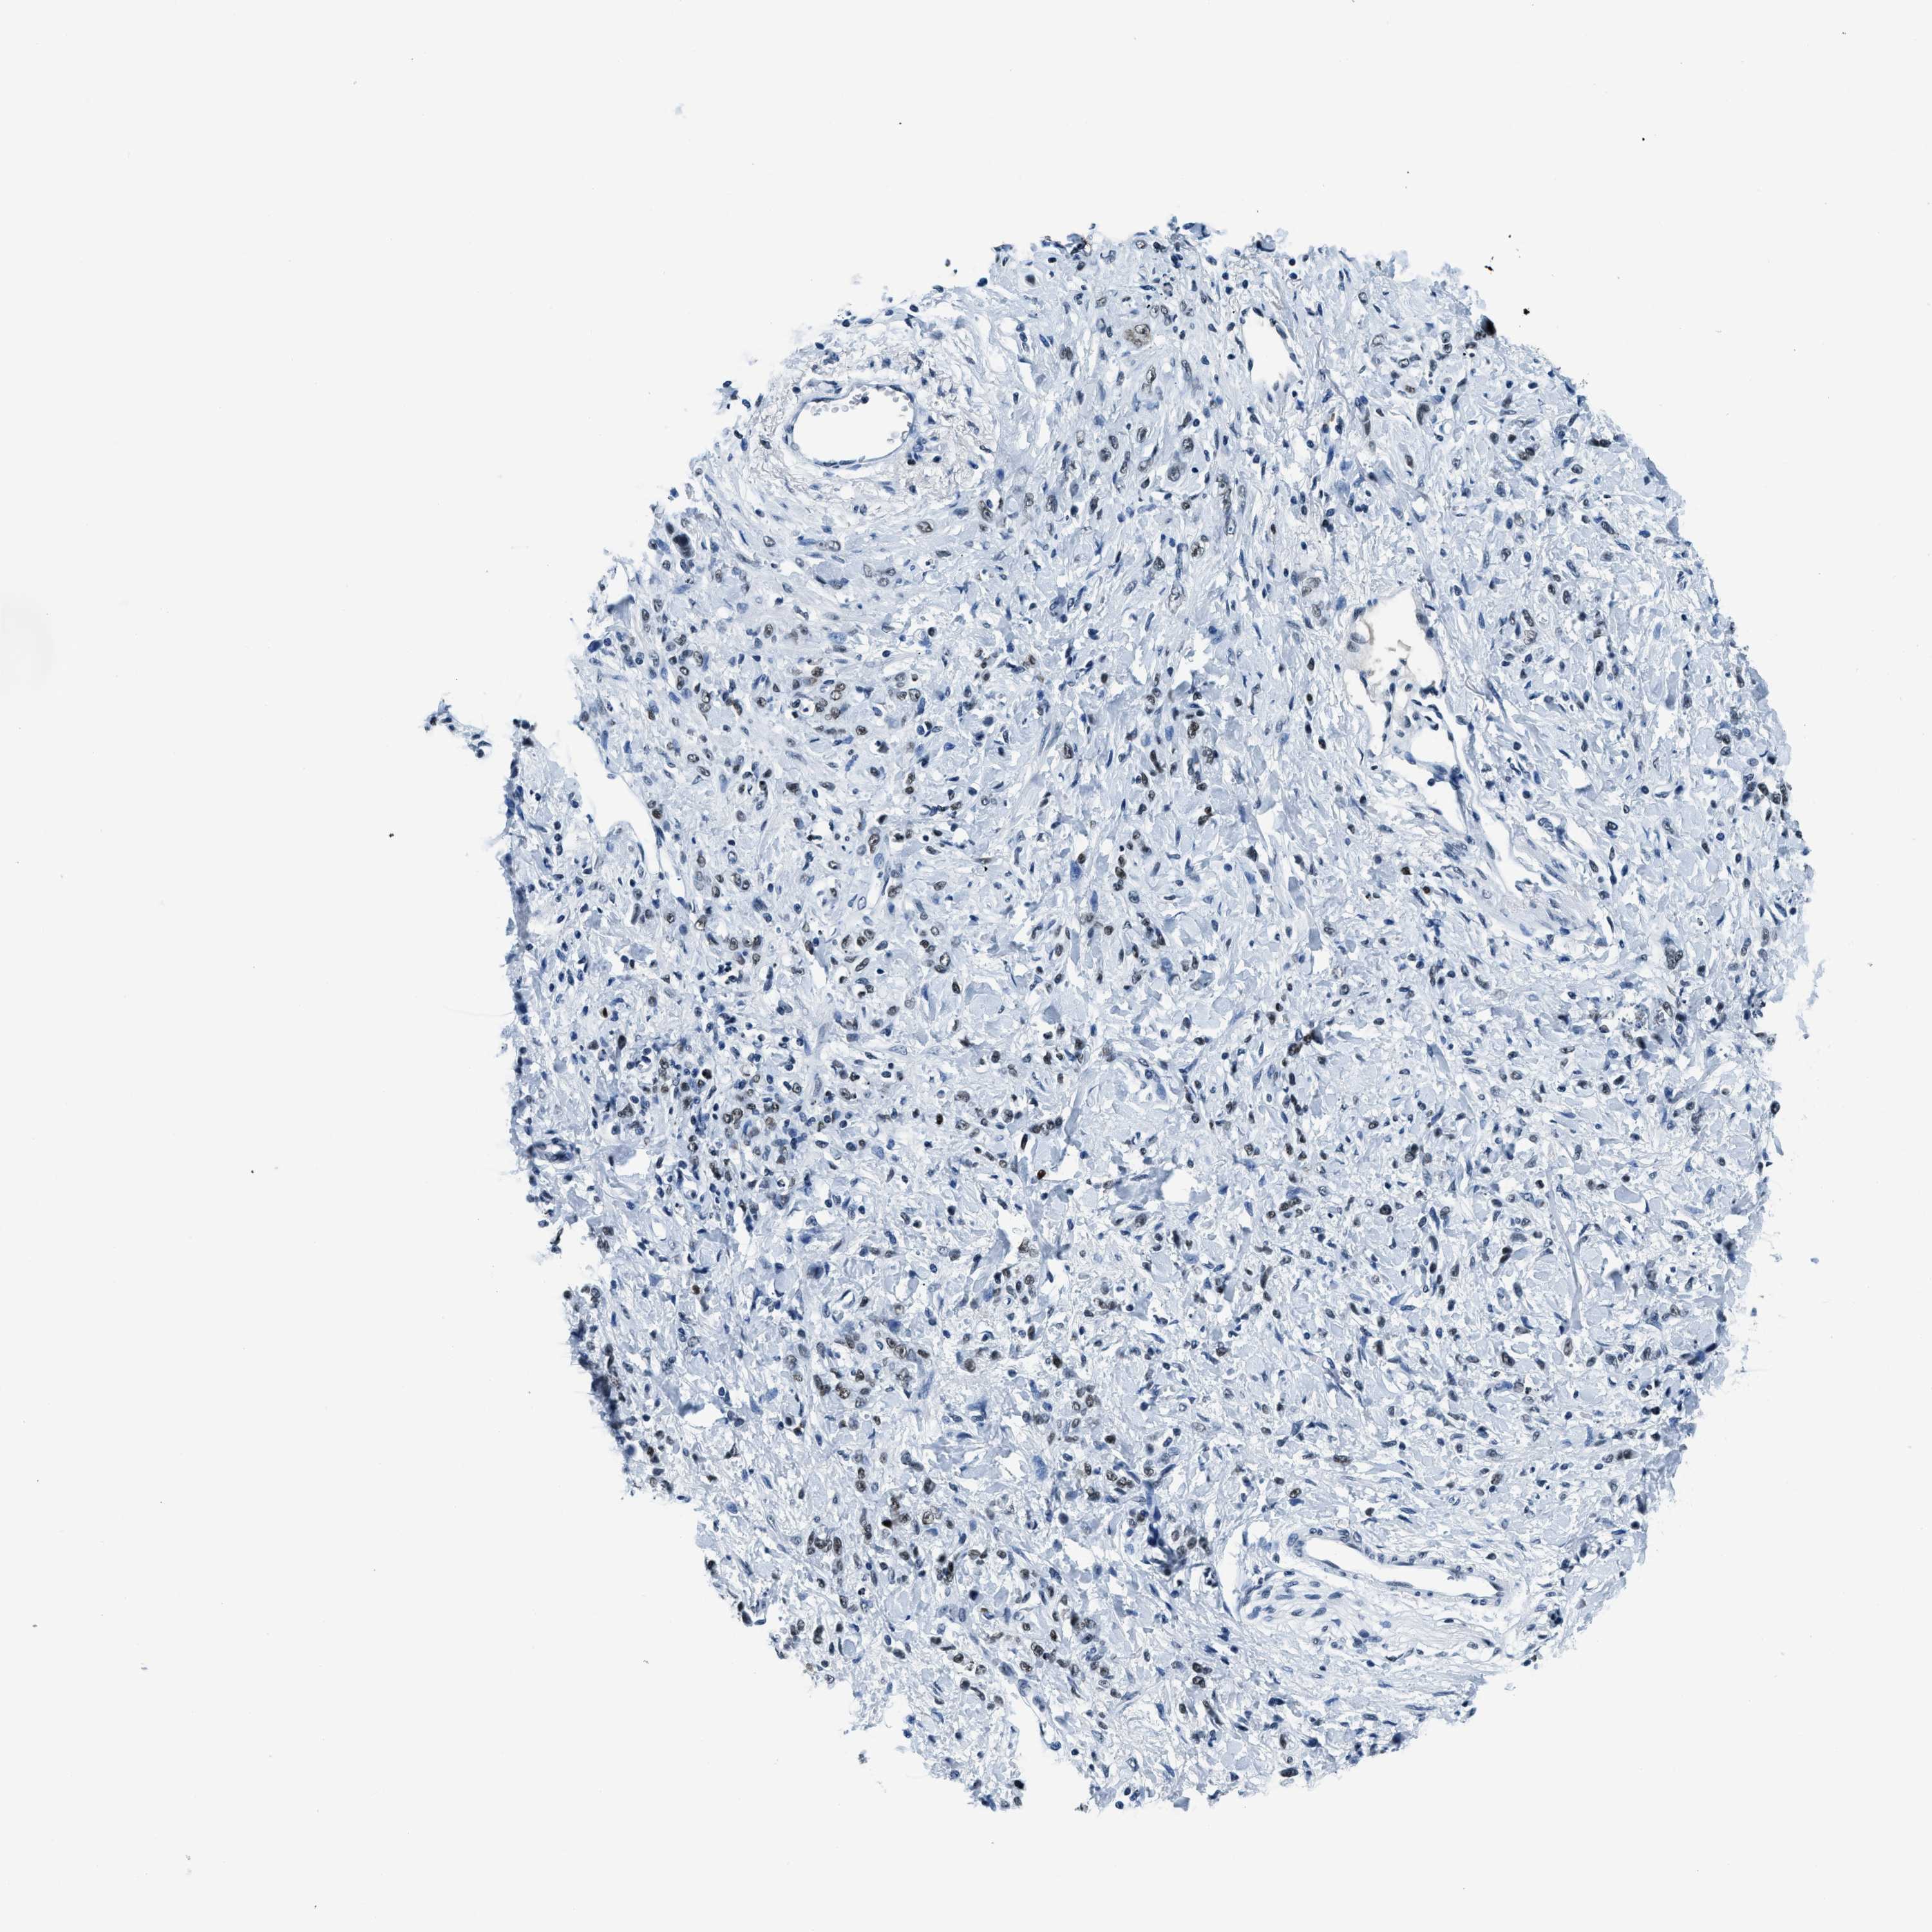

STOMACH CANCER - Protein expressioni

A mouse-over function shows sample information and annotation data. Click on an image to view it in a full screen mode. Samples can be filtered based on level of antibody staining by selecting one or several of the following categories: high, medium, low and not detected. The assay and annotation is described here.

Note that samples used for immunohistochemistry by the Human Protein Atlas do not correspond to samples in the TCGA dataset.

Antibody stainingi

Antibody staining in the annotated cell types in the current human tissue is reported as not detected, low, medium, or high, based on conventional immunohistochemistry profiling in selected tissues. This score is based on the combination of the staining intensity and fraction of stained cells.

Each image is clickable and will lead to virtual microscopy that enables deeper exploration of all samples and also displays staining intensity scores, fraction scores and subcellular localization as well as patient and tissue information for each sample.

Antibody HPA019039

Antibody CAB009058

Staining

High

Medium

Low

Not detected

Intensity

Strong

Moderate

Weak

Negative

Quantity

>75%

75%-25%

<25%

None

Location

Nuclear

Cytoplasmic/membranous

Cytoplasmic/membranous,nuclear

Adenocarcinoma, NOS